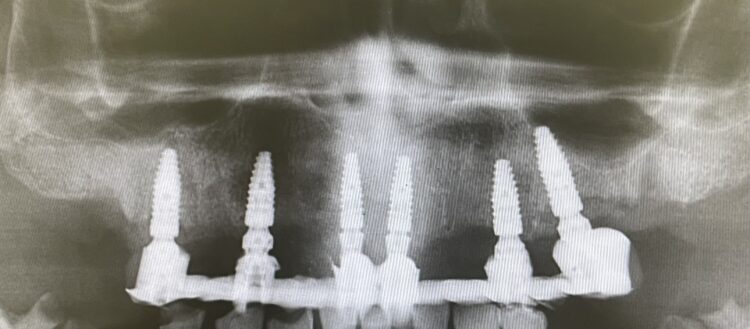

The implant beds were then prepared with the surgical guide in situ. Six CONELOG® Progressive-Line implants from BioHorizons Camlog were placed in accordance with the predetermined positions, depths and angulations. These implants were selected for this case because they feature an optimal thread design and tapered figure, promoting high primary stability – which is essential in full arch reconstruction cases.

The implants were placed through the guide for better accuracy and precision. A surgical primary stability of >35Ncm was achieved for each implant. Once the implants were placed, the surgical guide was removed, and the extraction of the remaining teeth was completed.

This phase of treatment concluded with radiographs to confirm accurate implant placement. The patient was also given standard post-operative oral hygiene and care instructions. He reported no complications or concerns during the review appointment a week later.

Based on the digital design and copying the approved provisional prosthesis, a zirconia overlay was milled. The overlaying zirconia superstructure was digitally designed to fit the metal substructure, accomplish a flawless finish line, avoid any undercuts and verify the path of insertion, thus facilitating the bonding procedures. The zirconia superstructure was bonded with the titanium substructure using a self-curing luting composite. The final polished screw-retained prosthesis was delivered and torqued to 30Ncm and the radiographic assessment was executed.